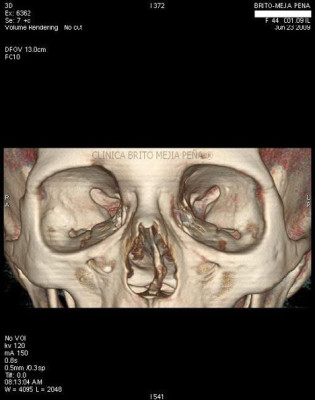

Cabeza y Cuello 2

Envíado por BMP Imágenes Diagnósticas

BMP Imágenes Diagnósticas